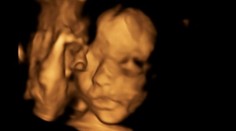

My ženy Unikátka operácia. Dieťa vybrali matke z maternice a po operácii vrátili späť Katarína Ács 12. 2. 2019